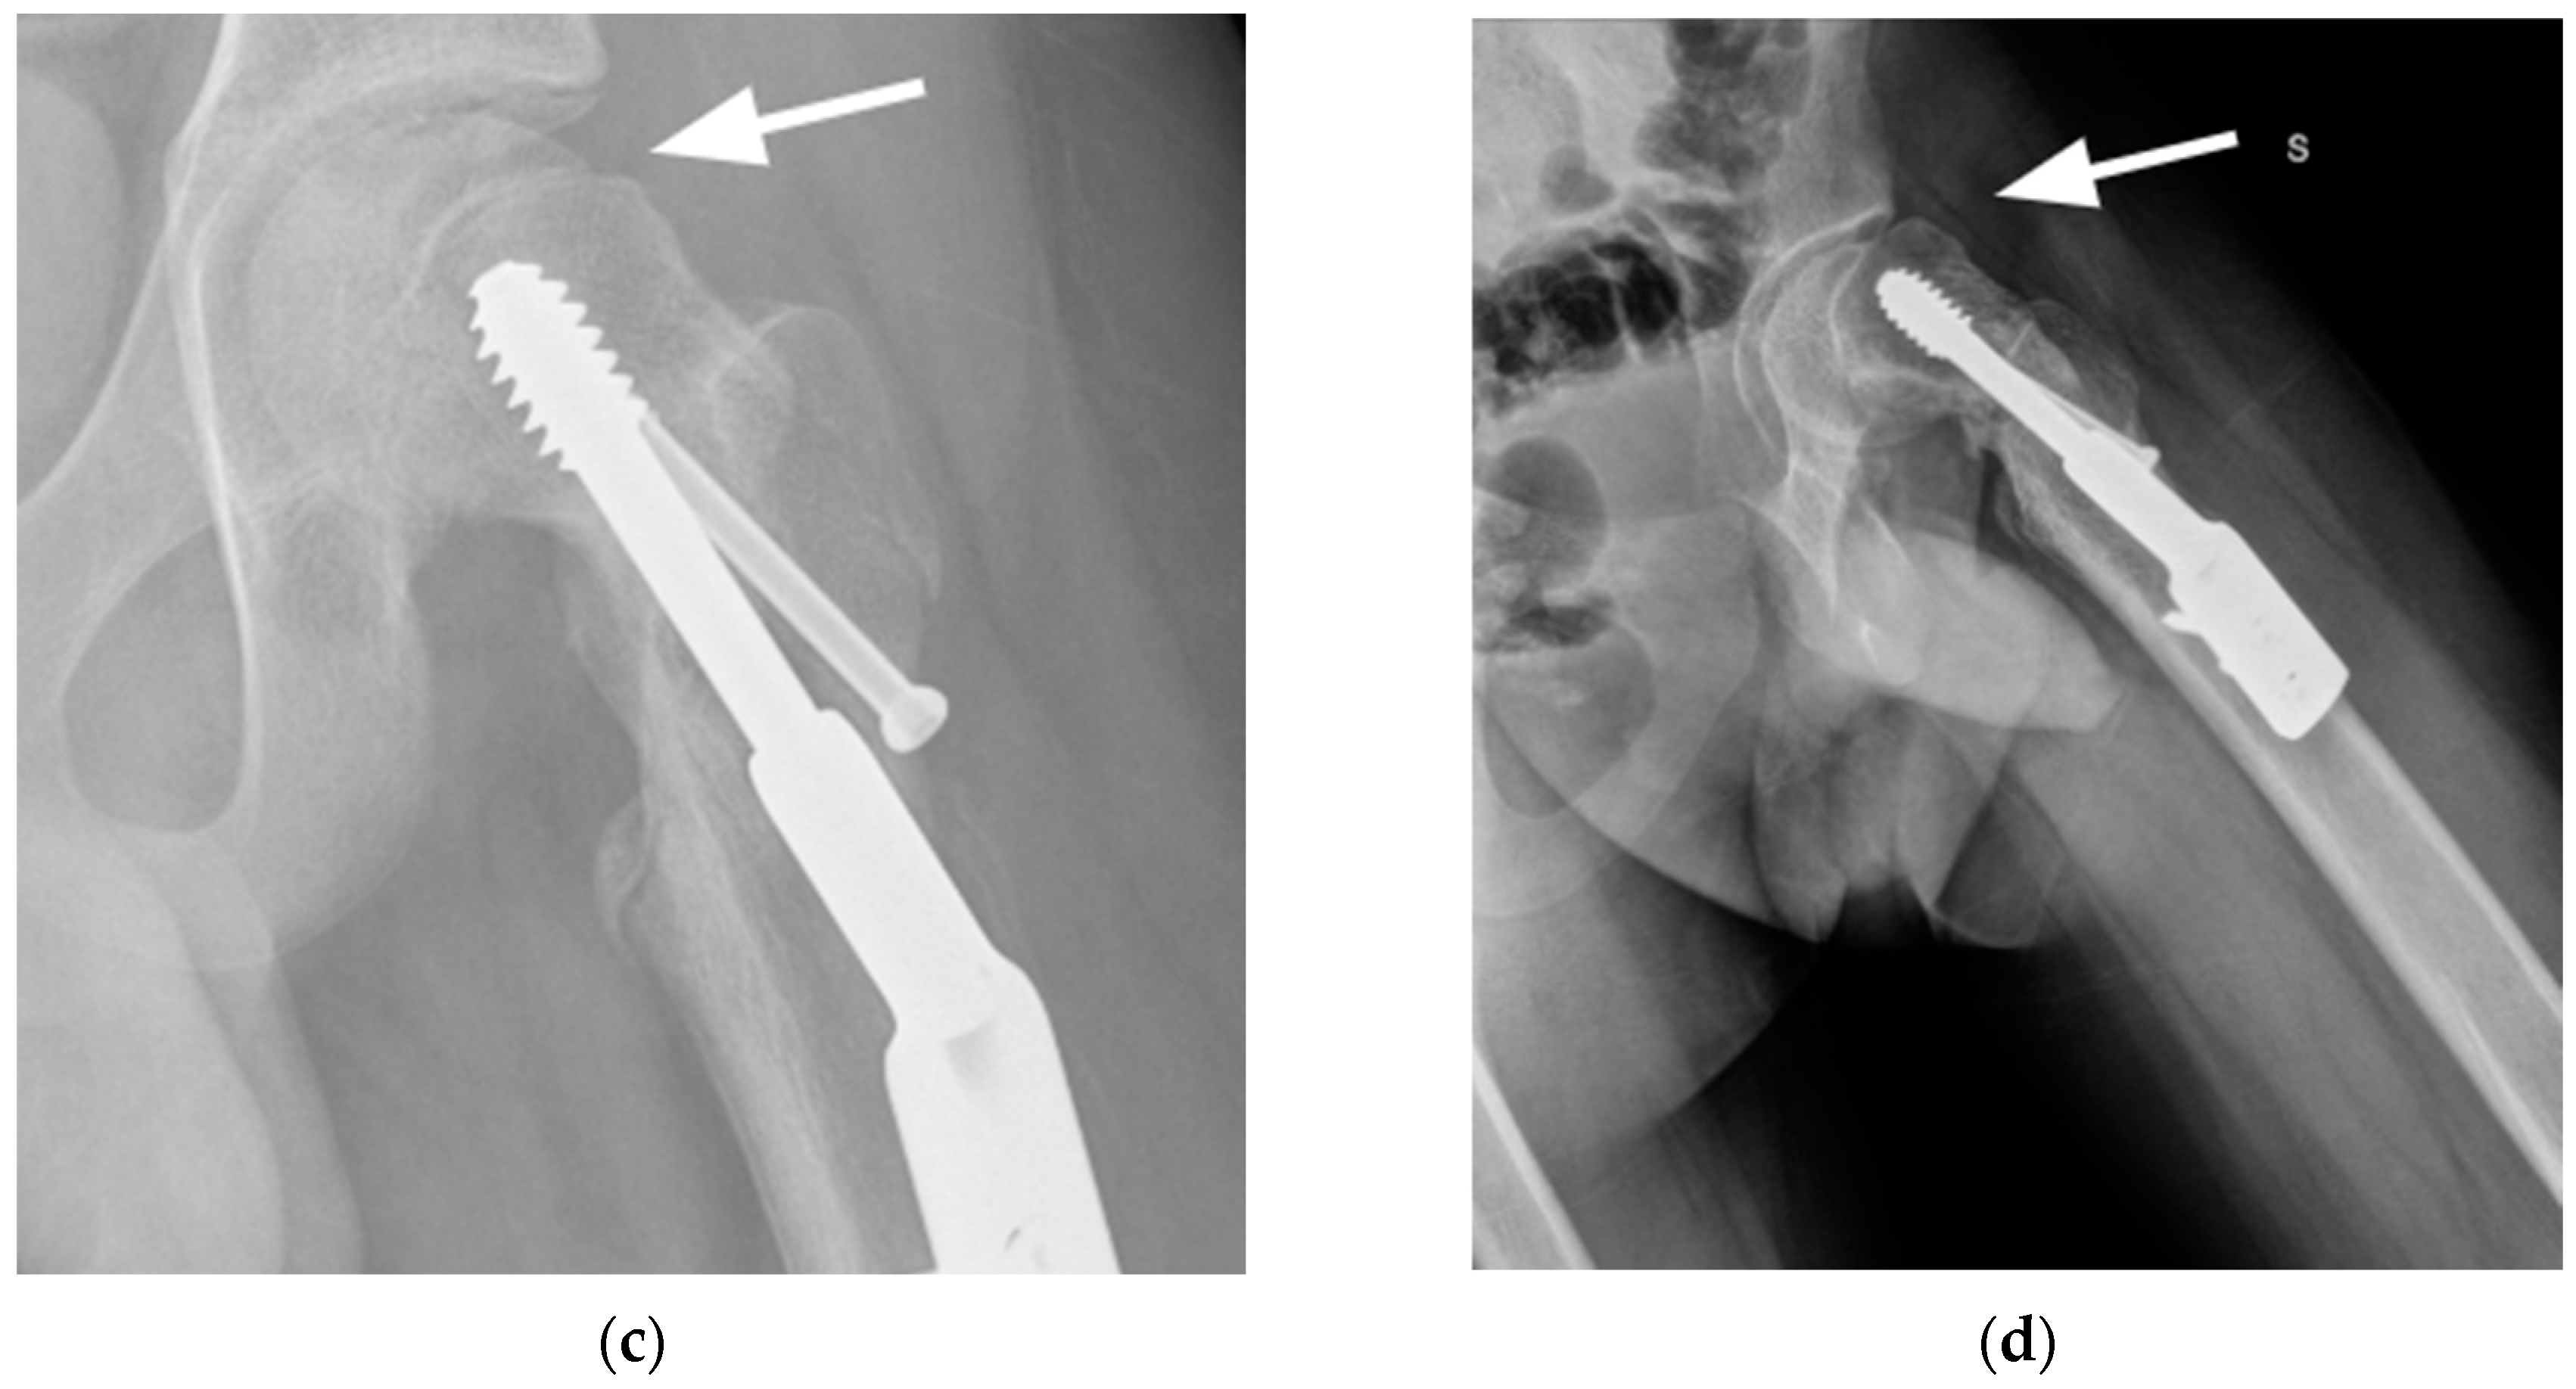

2. Case Presentation

2.2. Surgical Procedure

2.4. Results